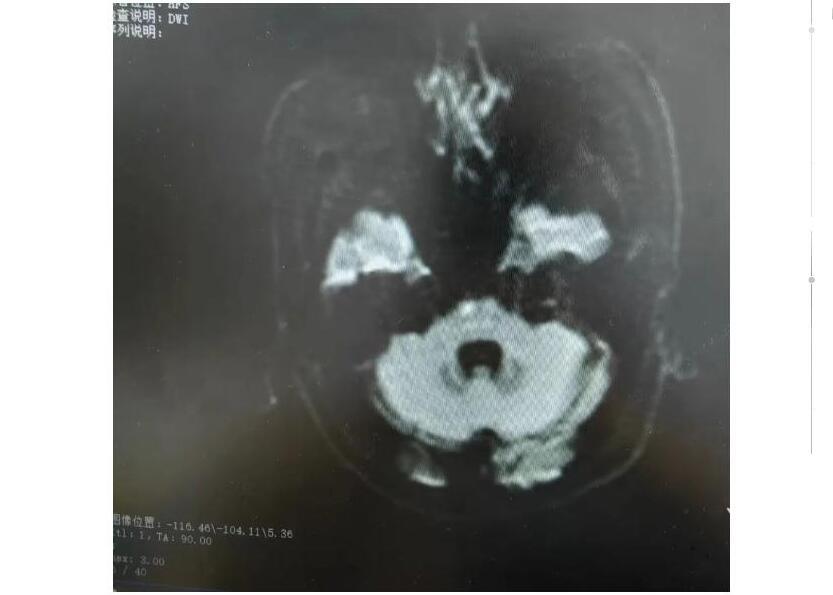

中新网黑龙江新闻5月24日电(刘璐)王女士(化名)突发左侧肢体无力,被家属紧急送至哈医大四院松北院区神经内科就诊,患者就诊时神志清楚,语言欠流利,左侧肢体肌力2级,经查头部核磁,桥脑新发梗死,被诊断为脑干梗死。神经内科刘路然主任为王女士制定了详细的治疗及康复方案,经过溶栓治疗2天后,患者病情基本平稳,左侧肢体肌力4级。